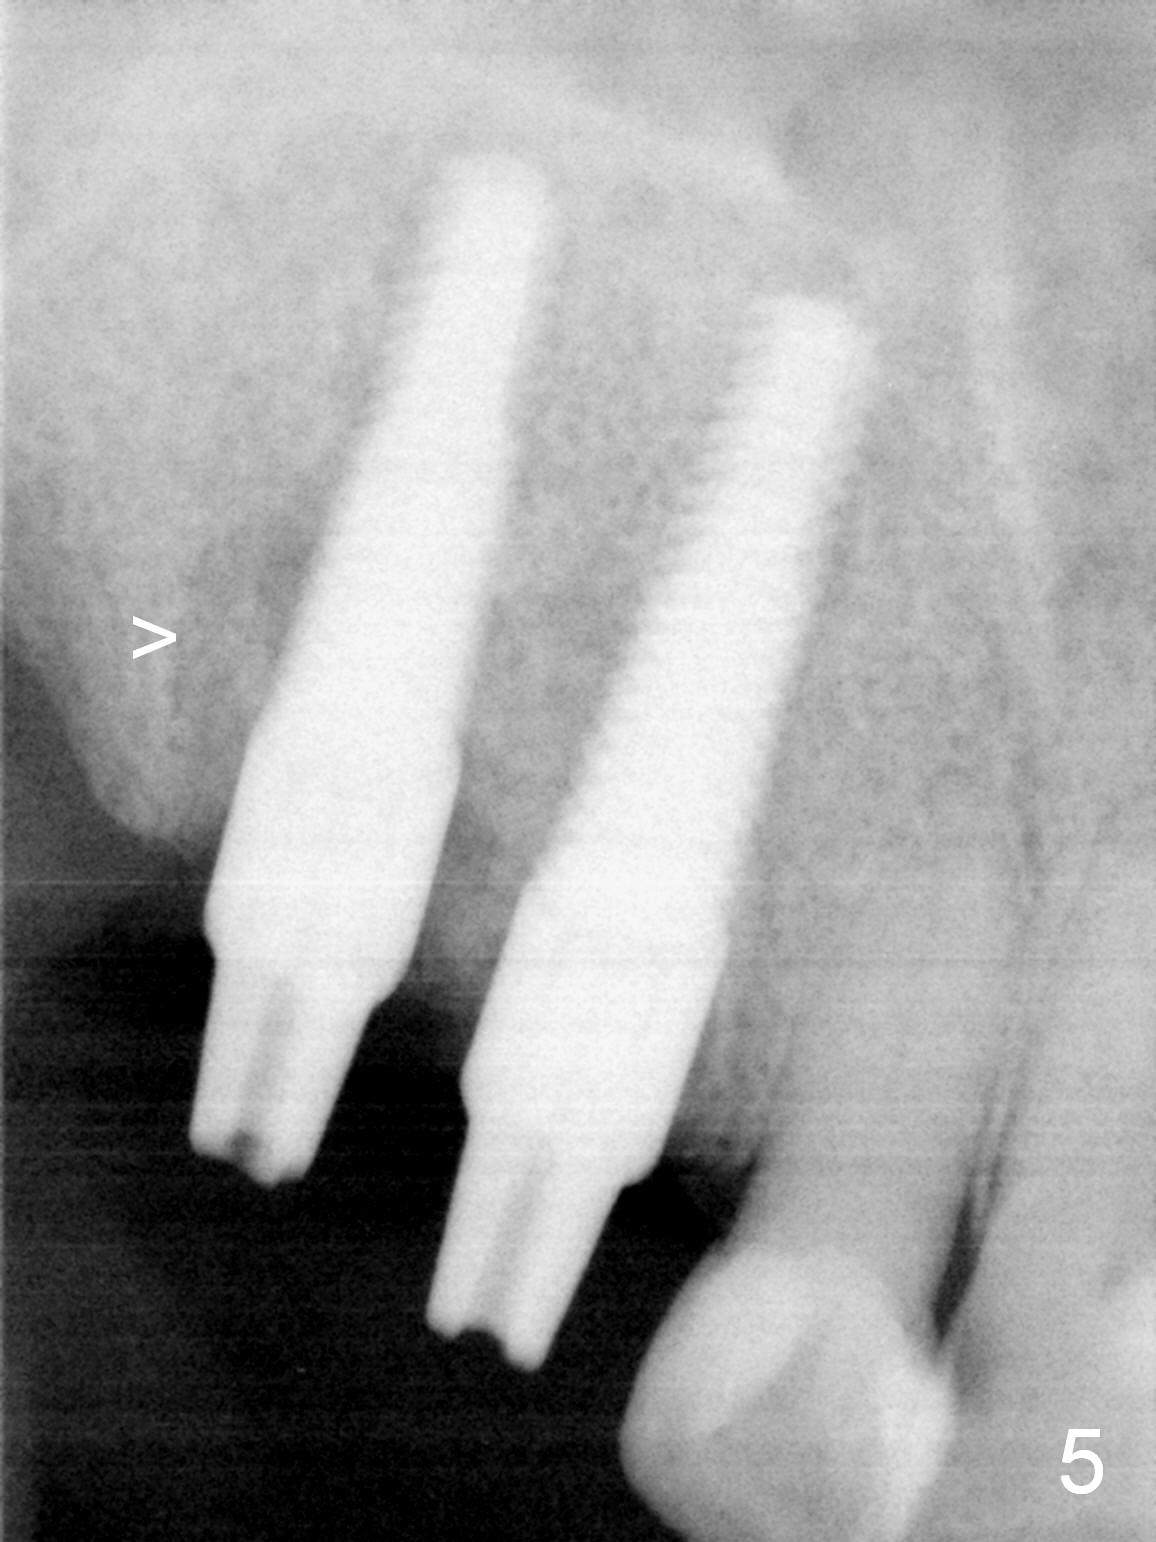

Several of CK's upper teeth (apparently in cross bite) are to be restored with implants (Fig.1). The first two are #5 and 6; note the oval roots (Fig.2). After extraction, and curettage, osteotomy starts in the palatal aspect of each socket. The 1st intraop PA shows that the trajectory at #6 is incorrect (Fig.3). After adjustment, osteotomies look parallel (Fig.4: D: 3.5x20 mm drill; T: 4.5x20 mm tap). This suggests how important it is to use parallel pins to check initial osteotomies for neighboring implants (Fig.3). The trajectory of the implants remains acceptable (Fig.5: 4.5x20 mm with insertion torque »60 Ncm); so is the position of the implants (as palatal as possible; Fig.6 (*: bone graft)). Immediate provisionals are fabricated in cross bite.

Bone density in the distal gap of #5 appears to have increased 3 months postop (Fig.7). Prior to definitive restoration cementation (3.5 months postop), the buccal plate does not collapse (Fig.8). There is no occlusal contact of the new restorations (Fig.9 *), probably due to bite discrepancy (Fig.10,11).